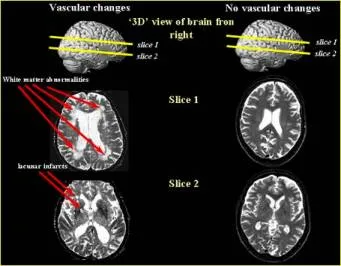

Any tissue deprived of circulation will die. Such tissue death is called myocardial infarction in the heart and cerebral infarction (or stroke) in the brain. Just as you can have a "silent" or asymptomatic heart attack, you can also have asymptomatic strokes if they are small enough. These show up on a CT scan or MRI as small white areas. Collect enough of these to impair thinking and we call it "multi-infarct dementia."

On the right is an MRI of a normal brain. The white areas you see represent normal fluid in the fissures between the gyri. The arrows on the image of the brain on the left indicate abnormal white areas, evidence of small strokes. These cerebral events often fail to cause the typical weakness and numbness of a larger stroke, but when enough occur, thinking becomes more difficult.